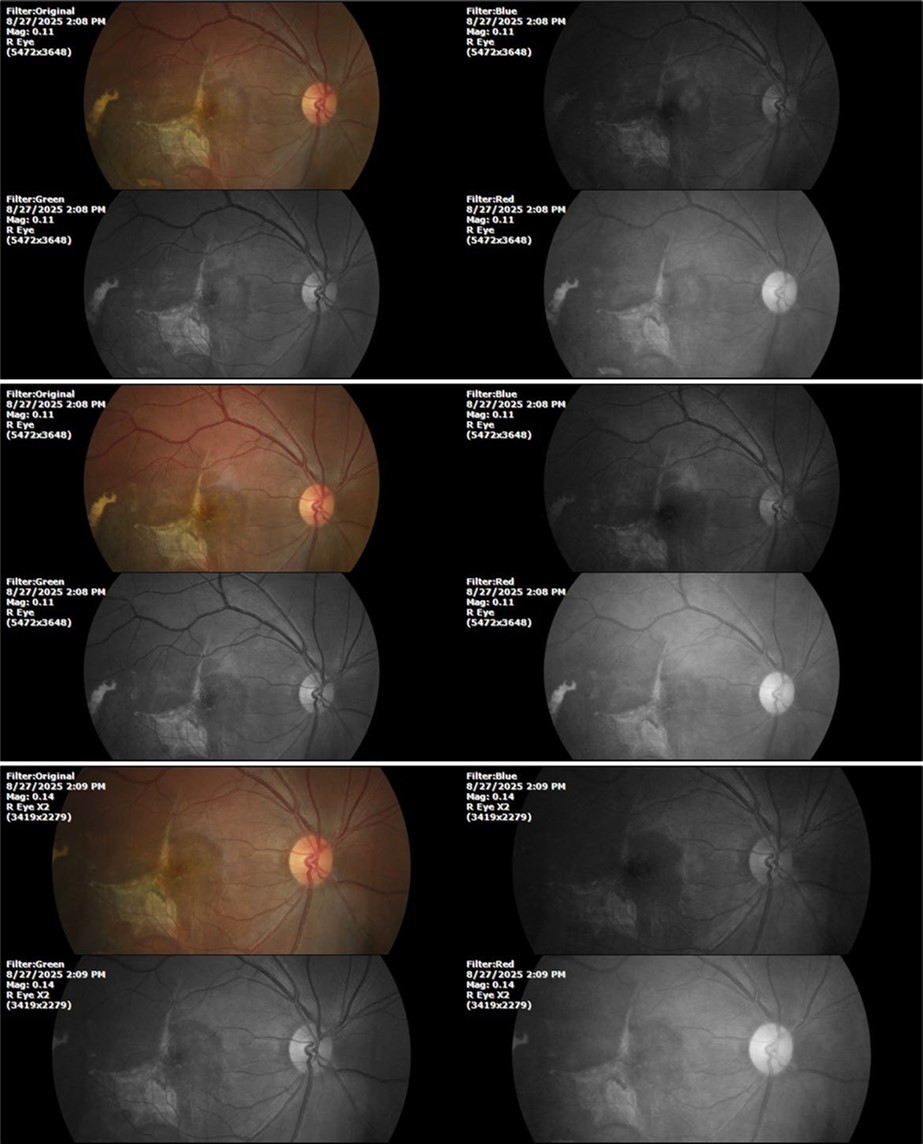

August 26, 2025

It's been fine, there's only a little veil that prevents it from seeing well completely, although it's very transparent (Figure 31, Figure 32, Figure 33, Figure 34, Figure 35, Figure 36).

Figure 31.The photograph of the right eye shows an almost normal mirror reflection, as well as a better pupillary dilation.

Figure 32.The macro photograph of the right eye shows us a cornea, anterior camera, and crystalline lens in very good condition.

Figure 33.The 3 previous photographs show that whitish mass has almost completely disappeared, and to date only a remnant remains on the left side of the photograph. The chorioretinal scar that is now observed corresponds to the area affected by the blunt trauma, which presumably caused rupture of Bruch's membrane. Fortunately, the macular region has recovered almost in its entirety, so the impairment in central vision was minimal.

Figure 8.The photograph of the superior temporal region of the retina of the right eye shows the extent of subretinal bleeding as well as retinal edema.

Figure 9.The extent of bleeding, mainly subretinal, is extensive and of significant volume, suggesting choroid rupture in this area.

Figure 10.The location of the bleeding is mainly subretinal, although blood is seen in minimal quantity in the vitreous body.

Figure 27.The three previous photographs of the right fundus show that the whitish mass composed mainly of phantom cells continues to decrease.